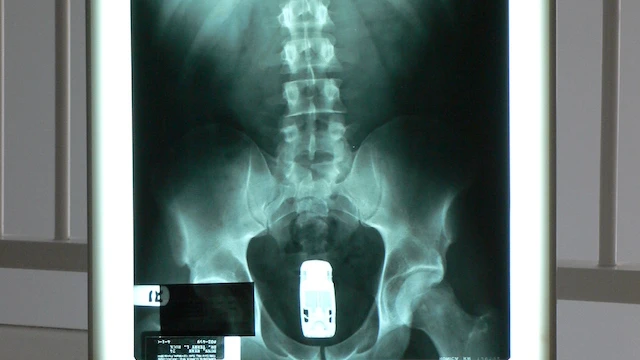

The human rectum has a depth of ~8 inches and a maximum diameter of 2.5 inches, giving us a volume of ~39 cubic inches, accounting for the narrowing of the cavity. The trickier part is finding an average size for a typical 1/64 scale Hot Wheels car. Thankfully, Mattel Australia has product dimensions for an assorted pack of cars, giving us what the manufacture understands at the average size overall. This gives us 2.95 inches in length, 1.18 in width and 0.98 in height. Using the volume of a rectangular prism, this gives us a volume of 3.41 cubic inches. Again, this volume calculation is assuming the cars are a liquid mass that forms to the walls of a rectum, but we will expand on this later. With the calculations we have now, 11 (rounded down from 11.4) Hot Wheels cars can fit in the human rectum. However, this number isn’t realistic, because it’s assuming the car takes up every bit of room in said rectum. I’ll redo the calculations but a little more complicated, assuming the cars are rectangular prisms and the rectum is a perfect cylinder.

Let’s hop into some CAD, why don’t we? Using Catia V5 and with some very basic modeling, the cylinder was modeled semi-accurately and the largest sized rectangle was placed inside. This rectangle has the dimensions of 1.56 inches long, 1.94 inches wide and 8 inches deep. This gives us a total volume of 24.21 cubic inches. Using the average volume of a Hot Wheels car, being 3.41 cubic inches, we can divide the two and find a total of 7 (rounded down) full Hot Wheels cars that can fit into the human rectum. Yes, I’m an engineer. Yes, I’m happy with how I spent my time today. Thank you for coming to my Ted Talk.